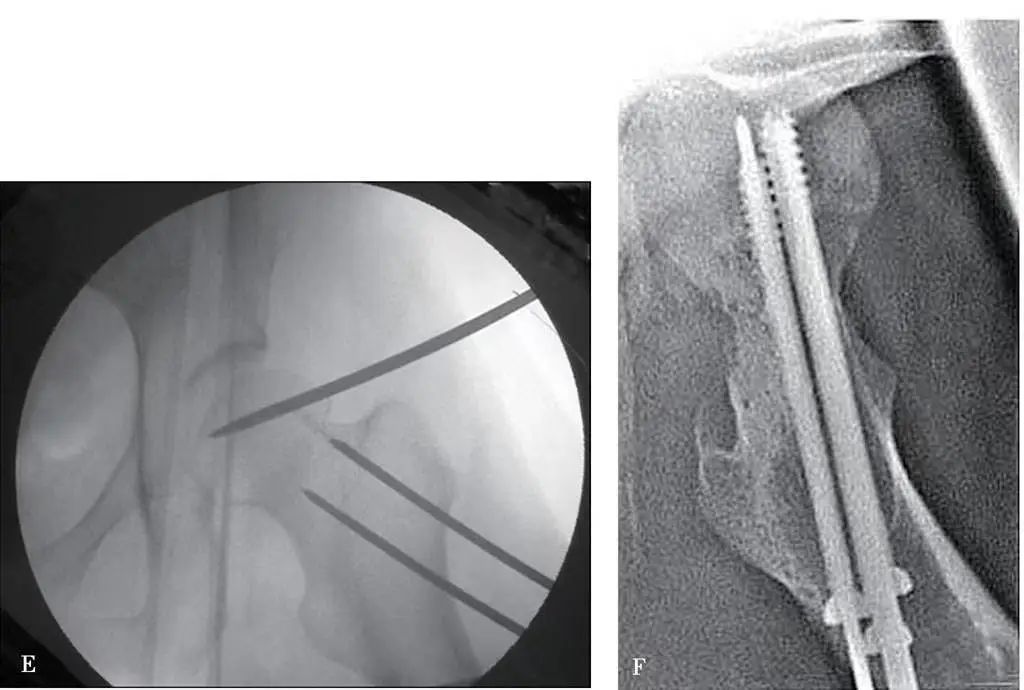

La méthode de réduction fermée décrite ci-dessus peut atteindre la réduction requise dans environ 98 % des fractures du col du fémur.Meilleur est l'alignement de la fracture, qu'elle soit fermée ou incisée, meilleur est le pronostic.Habituellement, le degré de luxation de la fracture montré sur la radiographie est inférieur au degré réel de luxation de la fracture.Étant donné que l'alignement de la fracture affecte directement la cicatrisation de la fracture et la possibilité de nécrose de la tête fémorale, il est nécessaire d'avoir un jugement correct du film radiographique après l'alignement de la fracture.Si la courbe en forme de S n'est pas lisse ou interrompue, cela indique que la fracture du col fémoral n'a pas atteint le repositionnement anatomique (Figure 2).

Figure 2 Radiographies de fracture du col du fémur avec courbure externe continue en alignement anatomique et courbure externe interrompue en alignement non anatomique